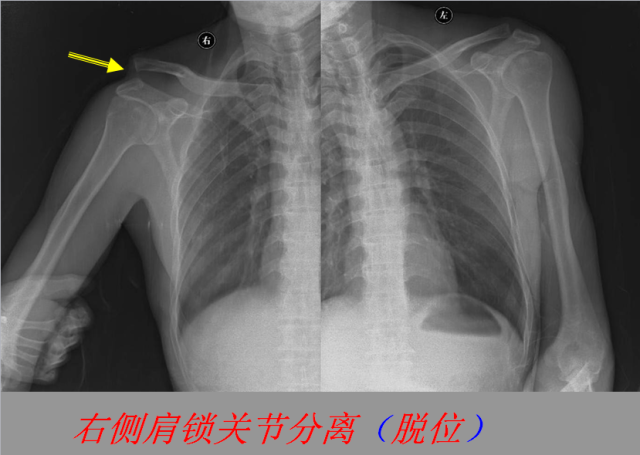

关节脱位篇

02

定义:关节脱位是暴力、关节感染、附近软组织挛缩或先天骨发育障碍造成的关节对位关系部分或完全脱离,即为半脱位或脱位。临床上以创伤性脱位*常见。